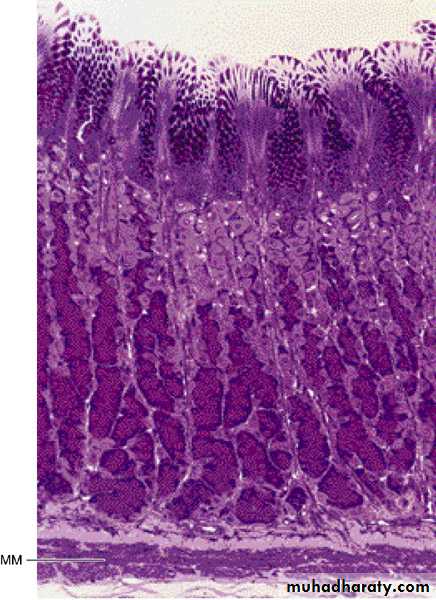

• Photomicrograph of a section of

• the gastric glands in the fundus of• the stomach. Note the superficial

• mucus-secreting epithelium.

• Parietal cells (light-stained)

• predominate in the mid and upper

• regions of the glands; chief (zymogenic)

• cells (dark-stained) predominate in the

• lower region of the gland. MM,

• muscularis mucosae. PT stain.

• Low magnification.